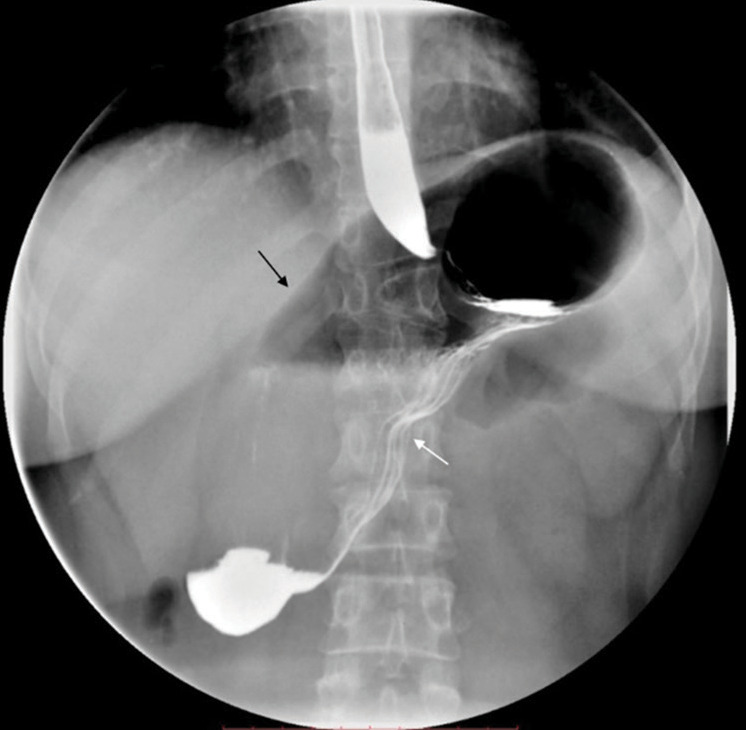

Portal vein (PV) anomalies are rare during embryonic development, with very few cases of duplicated PVs reported. This case reveals a new PV trunk anomaly, where computed tomography venography imaging shows three portal veins. The superior mesenteric vein and inferior mesenteric vein join to form a trunk that divides into two branches: One entering the liver (PV1) and the other ascending to join the splenic vein. The splenic vein then divides into two branches in the neck of the pancreas (PV2 and PV3), both entering the liver. The three PVs vary in thickness and all enter the liver through the first hepatic portal. Understanding the normal structure and anatomy of the PV is important for successful surgical planning. This case involves three main trunks of the PV, which is an extremely rare type of PV duplication anomaly. Reporting this case aims to enhance the awareness and understanding of PV duplication anomalies among clinicians and radiologists.